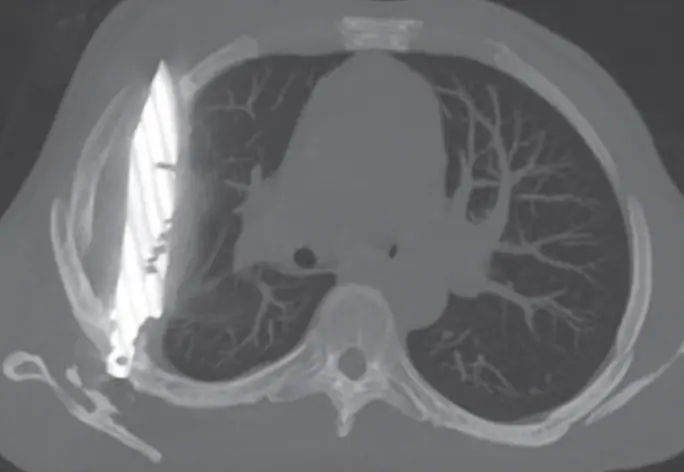

Doctors who examined him during this recent visit ordered an X-ray, which revealed a “retained metallic object” inside his chest. Further imaging confirmed the shocking finding: a knife blade had penetrated through his scapula (shoulder bone) and remained lodged deep within the chest cavity. Around the blade, a significant build-up of pus and necrotic tissue had formed, a sign that his body was beginning to respond to the foreign object after years of relative silence, according to PEOPLE.